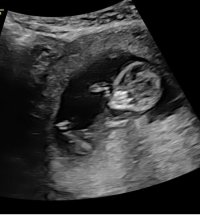

Kan se ut som jente, men veldig vanskelig å se på bildeneNoen som vil gjette kjønn? Uke 14+2